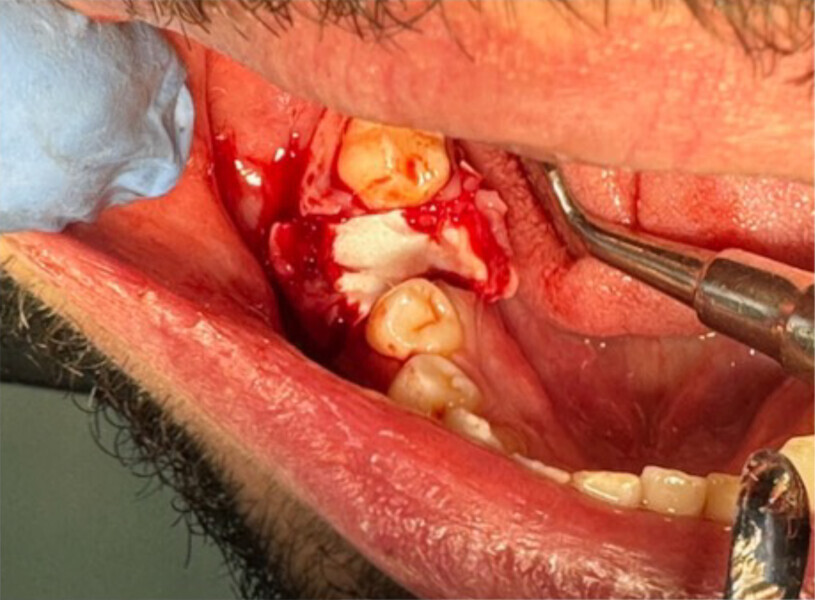

On pourra remarquer que la membrane a été volontairement laissée exposée, afin de ne pas lever de lambeau vestibulaire ou lingual. Grâce à ceci, nous avons pu conserver la totalité de cette muqueuse attachée, ce qui nous permettra d’obtenir un résultat esthétique bien meilleur lors de la reconstruction prothétique, qu’elle soit traditionnelle (bridge ou prothèse amovible) ou sur implants, en permettant d’avoir un profil d’émergence le plus proche possible du naturel (Figs. 4–8).

Dans notre cas, la pose d’implant a été privilégiée sur ce patient, jeune, avec des dents saines de part et d’autre de l’avulsion.

CBCT préimplantaire

Lors de la réouverture pour la pose de l’implant, nous avons pu constater que la hauteur de l’alvéole a été préservée, et la constitution de néo os alvéolaire de belle consistance nous a permis la pose de l’implant en toute sécurité (Figs. 9 et 10).